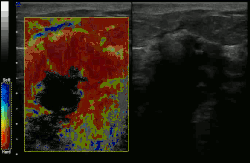

An ARFI image of a thyroid nodule in the right thyroid lobe. The shear wave speed inside the box is 6.24 m/s, which is reflective of a high stiffness. Histology revealed papillary carcinoma.

Acoustic radiation force impulse imaging (ARFI)[5] uses ultrasound to create a qualitative 2-D map of tissue stiffness. It does so by creating a 'push' inside the tissue using the acoustic radiation force from a focused ultrasound beam. The amount the tissue along the axis of the beam is pushed down is reflective of tissue stiffness; softer tissue is more easily pushed than stiffer tissue. ARFI shows a qualitative stiffness value along the axis of the pushing beam. By pushing in many different places, a map of the tissue stiffness is built up. Virtual Touch imaging quantification (VTIQ) has been successfully used to identify malignant cervical lymph nodes.[6]